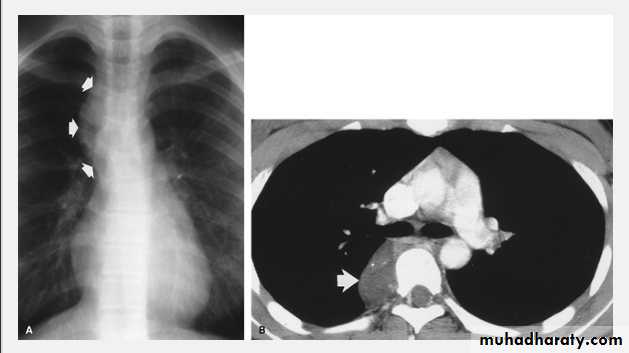

Tension pneumothorax.

On a posteroanterior chest x-ray (A), the left hemithorax is very dark or lucent because the left lung has collapsed completely (white arrows).

The tension pneumothorax can be identified because the mediastinal contents, including the heart, are shifted toward the right, and the left hemidiaphragm is flattened and depressed. A computed tomography scan done on a different patient with a tension pneumothorax (B) shows a completely collapsed right lung (arrows) and shift of the mediastinal contents to the left.